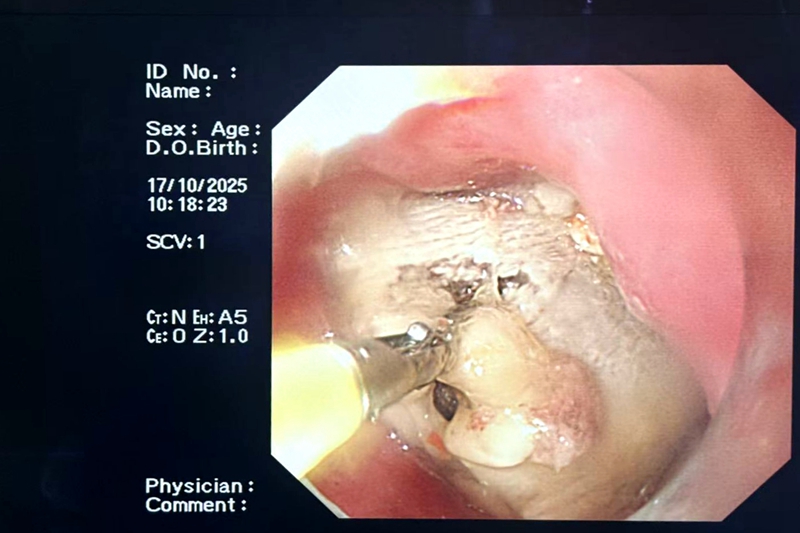

紧接着,医生火速安排床边胃镜检查,以便精准找到问题根源。果不其然,当胃镜镜头缓缓深入,在老人食道末端,一块未被充分咀嚼的 “排骨”牢牢卡在了管腔!正是这块排骨卡住食道后,在老人再进食时引发了剧烈的食物返流,返流物误吸入肺部,最终导致老人窒息、神志不清,还并发了双肺感染,生命一度垂危。

【胃镜下的排骨】

明确病因后,医护团队在胃镜的辅助下,成功消除这块“致命的排骨”。异物清除后,针对老人的双肺感染等并发症,医护团队又进一步制定了精细化的治疗方案,给予抗感染、营养支持等对症治疗。